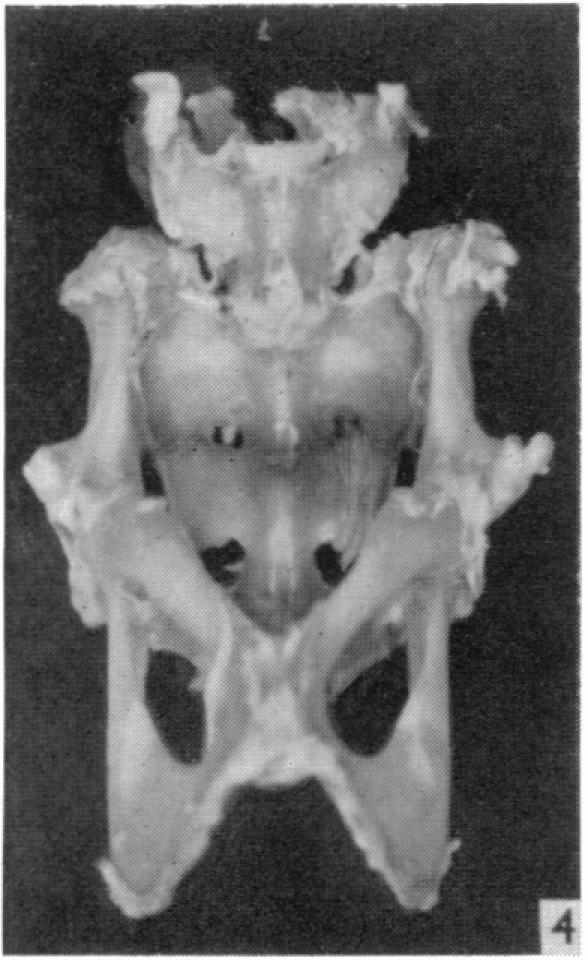

An experimental study of pelvic growth in the rat.

J Anat. 1958 Jul;92(3):483-8.